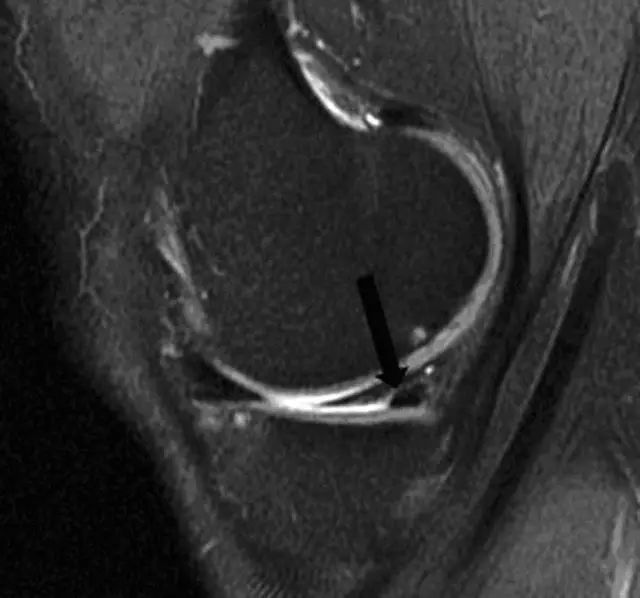

图 9 矢状面图像上可看到黑色箭头所指处,有一线性增强信号横贯内侧半月板后角,提示半月板斜行撕裂。